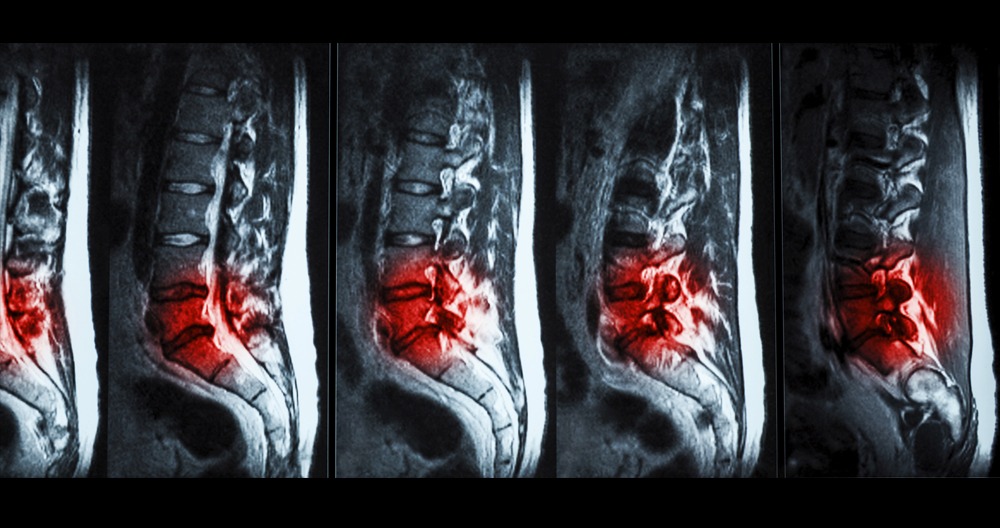

L5-S1 Herniated Disc

Low back pain (LBP), which is the most common problem, is a leading cause of disability. Herniated lumbar disc is one of many abnormalities that are associated with LBP. Lumbar discectomy is a procedure that has been performed regularly by neurosurgeons for many decades. Radiculopathy and back discomfort are the most common signs. Incontinence or rectal dysfunction may occur if there is urinary retention.

L5-S1 Disc Bulge And Disc Herniation Causes, Signs & Symptoms

The most common place for disc bulge, disc herniation (slipped disc) is in the lower back or lumbar spine. L4-L5 are the most common locations for a slipped disc to develop in the lower spine. L5-S1 is second in the list of possible involvement. L3-L4 is the most common site of herniated Lumbar discs.

Degenerative disc disease, which causes spinal disc herniation at L5 and S1, is the most common cause. Spinal disc diseases are all connected to disc degeneration. For L5-S1 to herniate, the disc must have had pre-existing degenerative conditions. Healthy discs will not herniate. Degenerated or damaged discs can lead to a herniated disc L5-S1. These are the most common causes of herniated spinal discs:

A herniated L5S1 disc could press and impinge nerves or the spinal cord. It can lead to pain, discomfort, and aches in the back, buttocks. It can also cause weakness, tingling and numbness in the legs, legs or knees.

- L5-S1 intervertebral disc. The disc between the vertebral bodies S5 and L5 is made of a gel-like material (nucleus pulposus). It is enclosed by a fibrous ring (annulus fibrosus). This disc acts as a shock absorber and cushion to protect the vertebrae when they move.

- Disc problems. L5-S1 is the most common level for lower back disc herniation. An disc with a steeper angle will experience greater shear stresses. This can increase the disc’s risk of injury or degeneration.